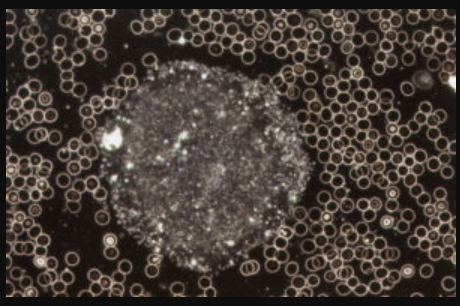

Manch Einer fragt sich warum werde ich krank und der Andere nicht. Mikroorganismen können sich unter bestimmten Verhältnissen einfach besser entwickeln. Ein gestörtes Körpermilieu ist der beste Nährboden für Erkrankungen. Genau hier setzt diese Untersuchungs- und Behandlungsmethode nach Prof. Dr. Enderlein an. Bei diesem Diagnoseverfahren wird mit Hilfe des Dunkelfeld-Mikroskops ein Tropfen Blut untersucht. Aufgrund der speziellen physikalischen Vorraussetzungen des Dunkelfeld-Mikroskops können Phänomene im Blut erkannt werden und so Rückschlüsse auf Veränderungen im Körpermilieu gezogen werden. Es wird die Anzahl, Form und Beweglichkeit der Weißen und roten Blutkörperchen untersucht, die Lage der Blutblättchen beurteilt und Erscheinungsformen im Plasma bestimmt.

Beispiele: